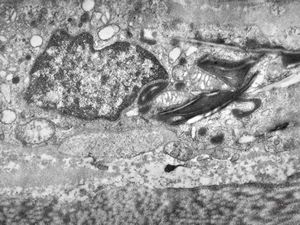

F,25y. | myopathy - atrophic and regenerating muscle cells

M,2y. | myopathy - regenerating muscle cell